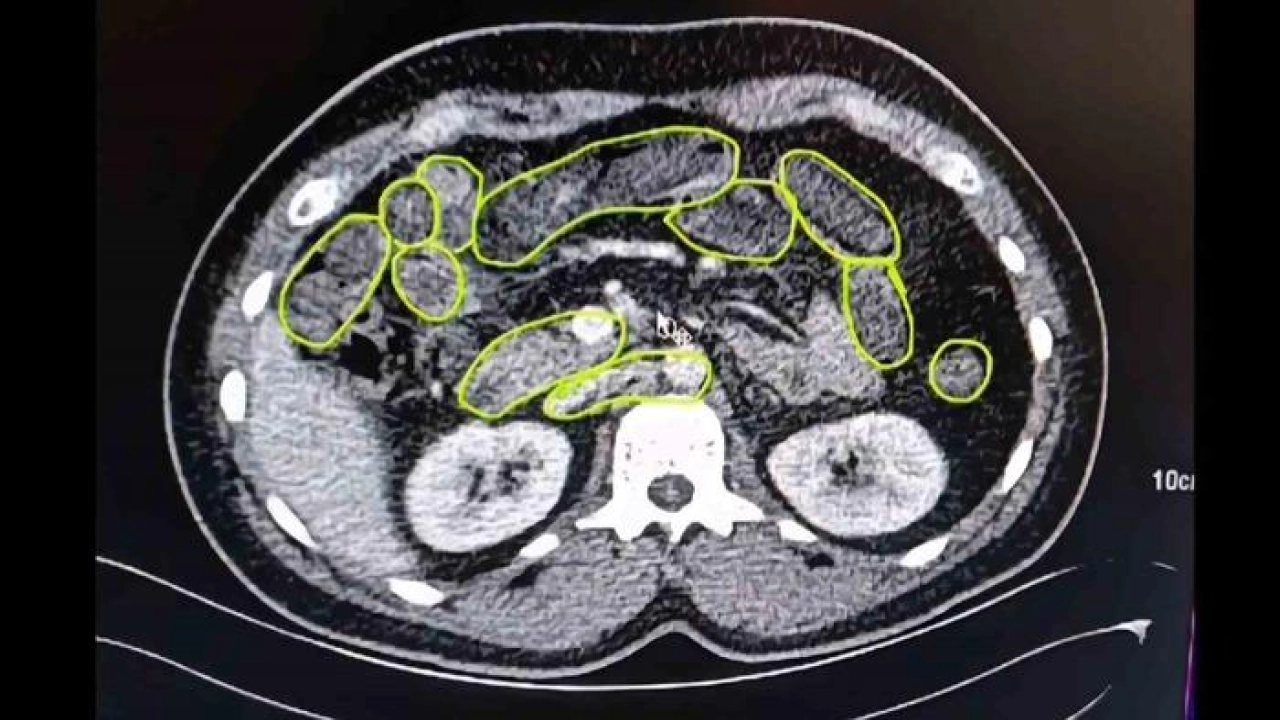

Şüphelilerin Kayseri Şehir Hastanesinde iç beden muayenesine alınırken, mide ve bağırsaklarında da çok miktarda kapsül şeklinde uyuşturucu olduğu değerlendirilen yabancı maddeler tespit edildi.